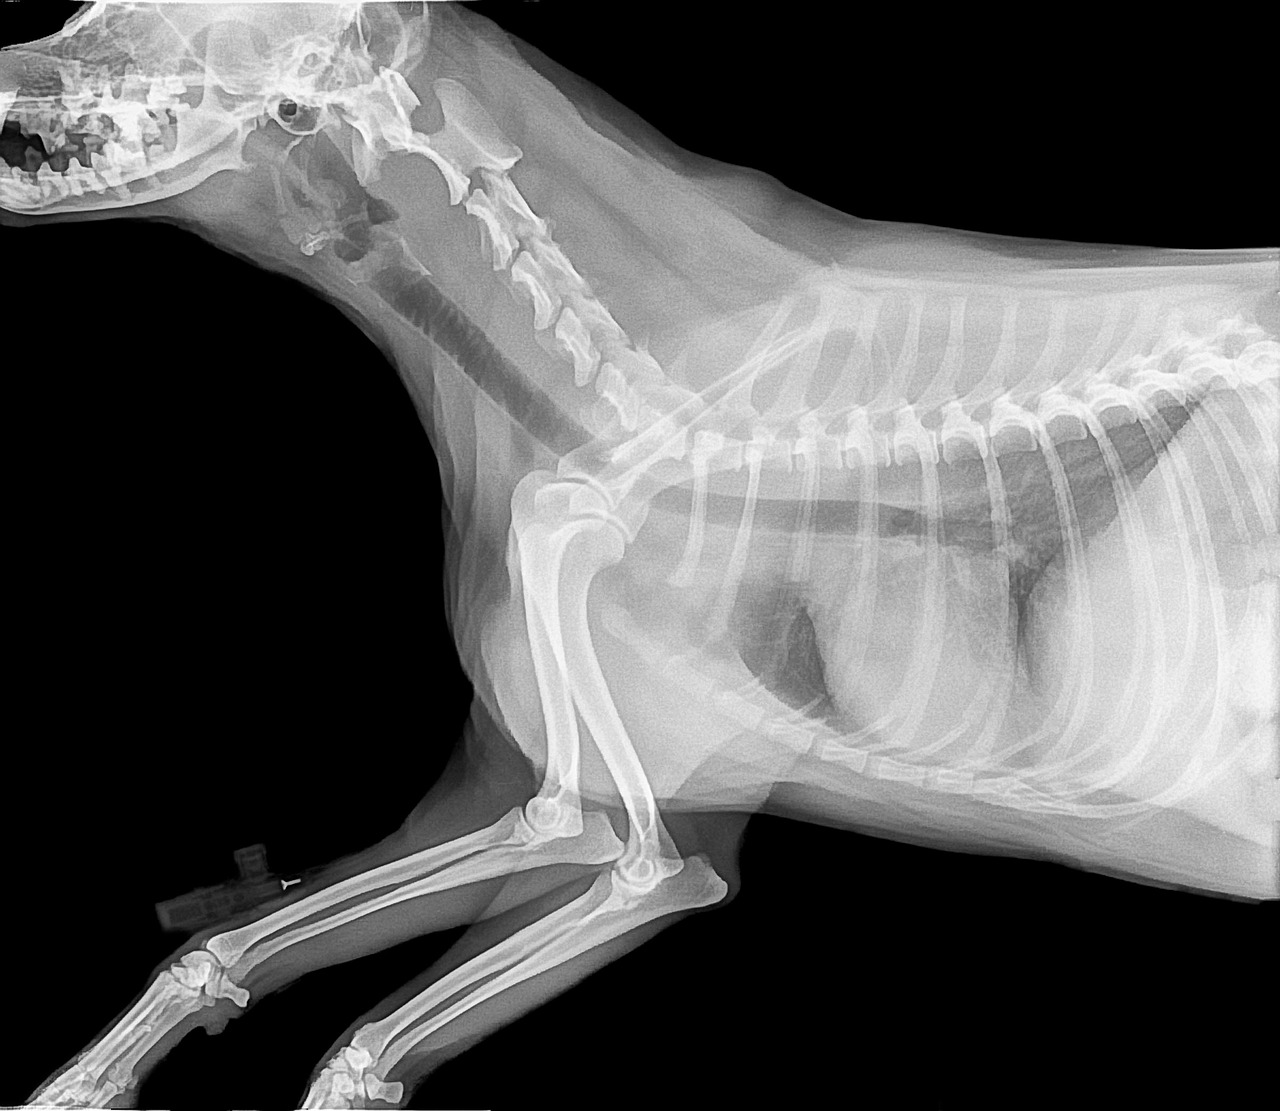

The relationship between hormones and bone density in pets is complex but essential for understanding overall health. Hormones like estrogen in females and testosterone in males significantly contribute to maintaining bone density. For dogs and cats, insufficient hormone levels often lead to conditions such as osteoporosis, characterized by weakened bones and increased fracture risk. Age-related hormonal changes can cause reductions in bone density, making senior pets more susceptible to injuries. Unlike humans, pets experience hormonal shifts differently, with conditions like spay or neuter surgeries affecting their hormone levels and subsequently their bone health. Owners should be aware of the signs of hormone-related bone issues. Symptoms include reluctance to engage in play, limping, or changes in behavior due to discomfort. Early diagnosis through hormonal testing and veterinary assessments can lead to effective treatment plans. Moreover, incorporating calcium and vitamin D into a pet’s diet supports bone strength. Alongside nutrition, regular exercise promotes bone density by enhanced blood circulation, ensuring the health of bone-forming cells. Using supplements cautiously, based on veterinary recommendations, aids bone maintenance without causing harm to pets.

Spaying and neutering are commonplace procedures that can significantly alter a pet’s hormonal levels. These surgeries effectively eliminate the production of specific hormones, which are critical to maintaining bone density. Consequently, pets that undergo these procedures may face an increased risk of developing bone-related issues later in life. Research suggests that spayed female dogs often experience a decline in estrogen levels, which directly correlates with bone density loss. Similarly, neutered male dogs may see changes in testosterone production, further impacting bone health. Therefore, pet owners should be proactive about monitoring their pet’s musculoskeletal health following spaying or neutering. Offering bone-strengthening supplements and a balanced diet can counteract some of these risks. Additionally, engaging pets in regular exercise is crucial; activities like running or playing fetch promote bone health through weight-bearing exercises. Regular veterinary visits post-surgery allow for timely evaluations of hormone levels and bone density. Awareness of the potential impacts of these surgeries empowers pet owners to take preventive measures, enhancing their pet’s long-term quality of life.